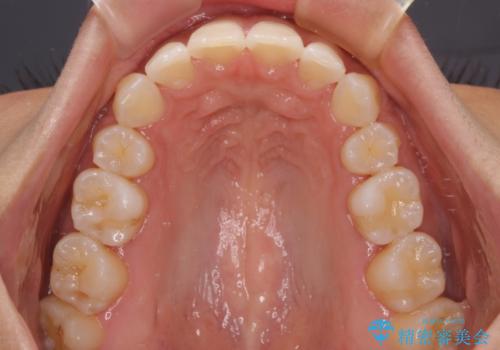

抜歯スペースに前歯を移動させることで歯の突出感が改善され、非常に唇が閉じやすい仕上がりとなりました。